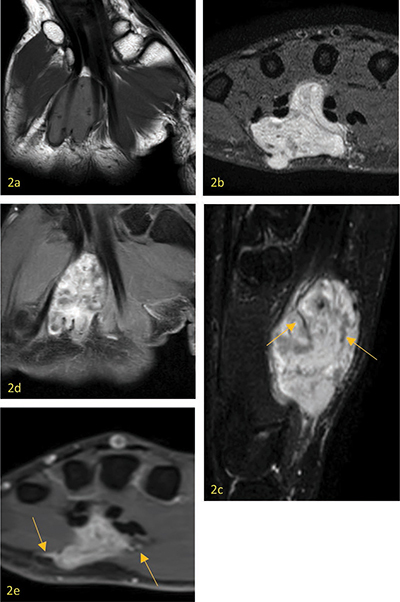

教学要点:血管网状肌瘤在磁共振成像上的表现为外周 T1 和 T2 高密度边缘、邻近的迂曲血管结构和暗网状征象。

Teaching point: Angioleiomyoma is defined on MR by a peripheral T1- and T2-hypointense rim, adjacent tortuous vascular structures, and a dark reticular sign.